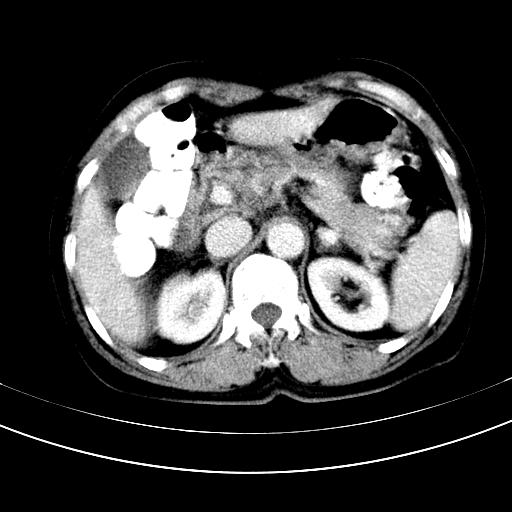

补充强化片

胃内见充盈缺损,建议行胃镜病理检查,如果胃内无占位,则肝内考虑左叶、尾叶为包膜型肝癌,如有则考虑为转移瘤,左侧肾上腺 明显增大,成结节改变,本人考虑转移瘤可能性大。

肾脏前方的是什么,肾上腺吗,

考虑:胃体小弯侧胃癌(或平滑肌瘤恶化或平滑肌肉瘤)伴肝转移,左侧肾上腺转移不除外.

胃癌肝内转移及肾上腺转移。

胃窦部占位伴肝及左肾上腺转移可能大,建议增强扫描。

肝左叶及尾叶低密度灶,增强有渐进性明显强化,考虑血管瘤。胃内“充缺”首先要排除异物(食物),变换体位可鉴别。增强时机抓的不好,还应该有延时像。

谢谢楼主的增强片子,平扫没发现左侧肾上腺的问题很不好意思,可惜片子只有门脉期,所以还只有猜,肝脏的病灶在门脉期部分强化,首先考虑为血管瘤(其他的用一种病不好解释)胃要喝水就好了现在不好说是否有问题,左肾上腺的问题考虑是肿瘤。

做了增强后,可以明确胃是没有肿瘤的,肾上腺也没有肿瘤.肝左叶的病灶首先考虑血管瘤,应该再延迟,肝尾状叶的病灶仍不能排除肝癌的可能性.